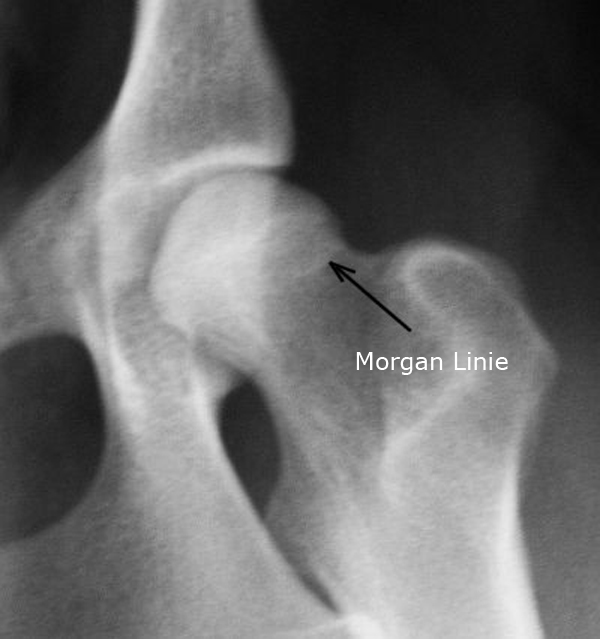

Eine Röntgenuntersuchung ist eine zuverlässige Möglichkeit, den Schwerengrad (es gibt 5 Schweregrade) der Erkrankung zu erkennen. Die Gelenke müssen Übersteckt werden, was beim Vorliegen einer HD starke Schmerzen verursacht. Da die Gelenke dabei stark überstreckt werden, muss sie unter eine Kurznarkose durchgeführt werden. Eine Vorraussetzung für eine aussagekräftige Diagnose ist die exakte Positionierung des Tieres in der Rückenlage mit gestreckten, paralell gelagerten Oberschenkeln und einem rechtwinkligen zum Strahlengang eingedrehten Kniescheiben. Zusätzliche Aufnahmen können in "Froschhaltung" der Oberschenkel oder seitlichen Strahlenhang erfolgen. Ein wesentliches Auswertungskriterium ist der Norberg-Winkel. Der Norberg-Winkel ist als der Winkel definiert, der zwischen der Verbindungslinie der Zentren der beiden Oberschenkelköpfe und dem vorderen Pfannenrand abgetragen wird. Mehr als 150° sollte er bei einem HD-freien Tier betragen. Weitere Beurteilungskriterien sind die Kongruenz von Oberschenkelkopf und Gelenkpfanne, die Weite des Gelenkspaltes, die Pfannenkontur, die Kontur des Oberschenkelkopfes sowie das Vorhandensein von Hinweisen auf arthrotische Prozesse wie walzenförmige Verdickungen des Oberschenkelhalses, Randwülste an der Gelenkpfanne, unter dem Knorpel befindliche Verdichtungen der Knochensubstanz im Pfannenbereich und die Anlagerung von Knochenmaterial 8 Osteophyt) am Ansatz der Gelenkkapsel (Morgan-Linie). Die Morgan-Linie ist ein sensitiver Frühmarker für eine Instabilität im Hüftgelenk. Für die züchterische Auswertung von HD-Aufnahmen ist im VDH nur durch von den Rassezuchtverbänden zugelassene Gutachter möglich, an die der Tierarzt die Röntgenbilder schicken muss.

Morgan-Linie

Quelle: rhodesianridgeback-bb.de